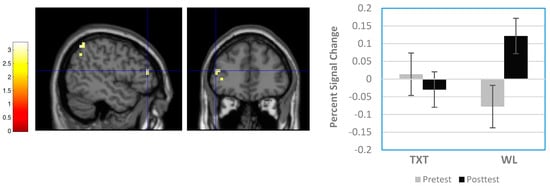

3.3.1. Whole Brain Results

3.3.2. Region-of-Interest Results

| Waitlist > Treatment | Right medial frontal gyrus | 8 | 8 | 24 | 52 | 2.54 | 0.350 | 0.006 | 12 |

| Left frontal subgyral | WM | −24 | 0 | 32 | 2.64 | 0.350 | 0.004 | 15 | |

| Right cingulate gyrus | 32 | 16 | 20 | 28 | 2.85 | 0.350 | 0.002 | 30 | |

| Left cingulate gyrus | 24 | −12 | −16 | 40 | 2.78 | 0.350 | 0.003 | 12 | |

| Right putamen | 24 | 20 | −16 | 2.99 | 0.350 | 0.001 | 21 | ||

| Right superior temporal gyrus | 22 | 56 | −56 | 16 | 3.19 | 0.350 | 0.001 | 10 | |

| Group X Time Interactions | |||||||||

| Right superior frontal gyrus | 6 | 16 | 12 | 56 | 2.75 | 0.677 | 0.003 | 26 | |

| Left middle frontal gyrus | 46 | −48 | 40 | 16 | 2.58 | 0.677 | 0.005 | 14 | |

| Left inferior parietal lobule | 40 | −56 | −40 | 52 | 2.84 | 0.677 | 0.002 | 17 | |